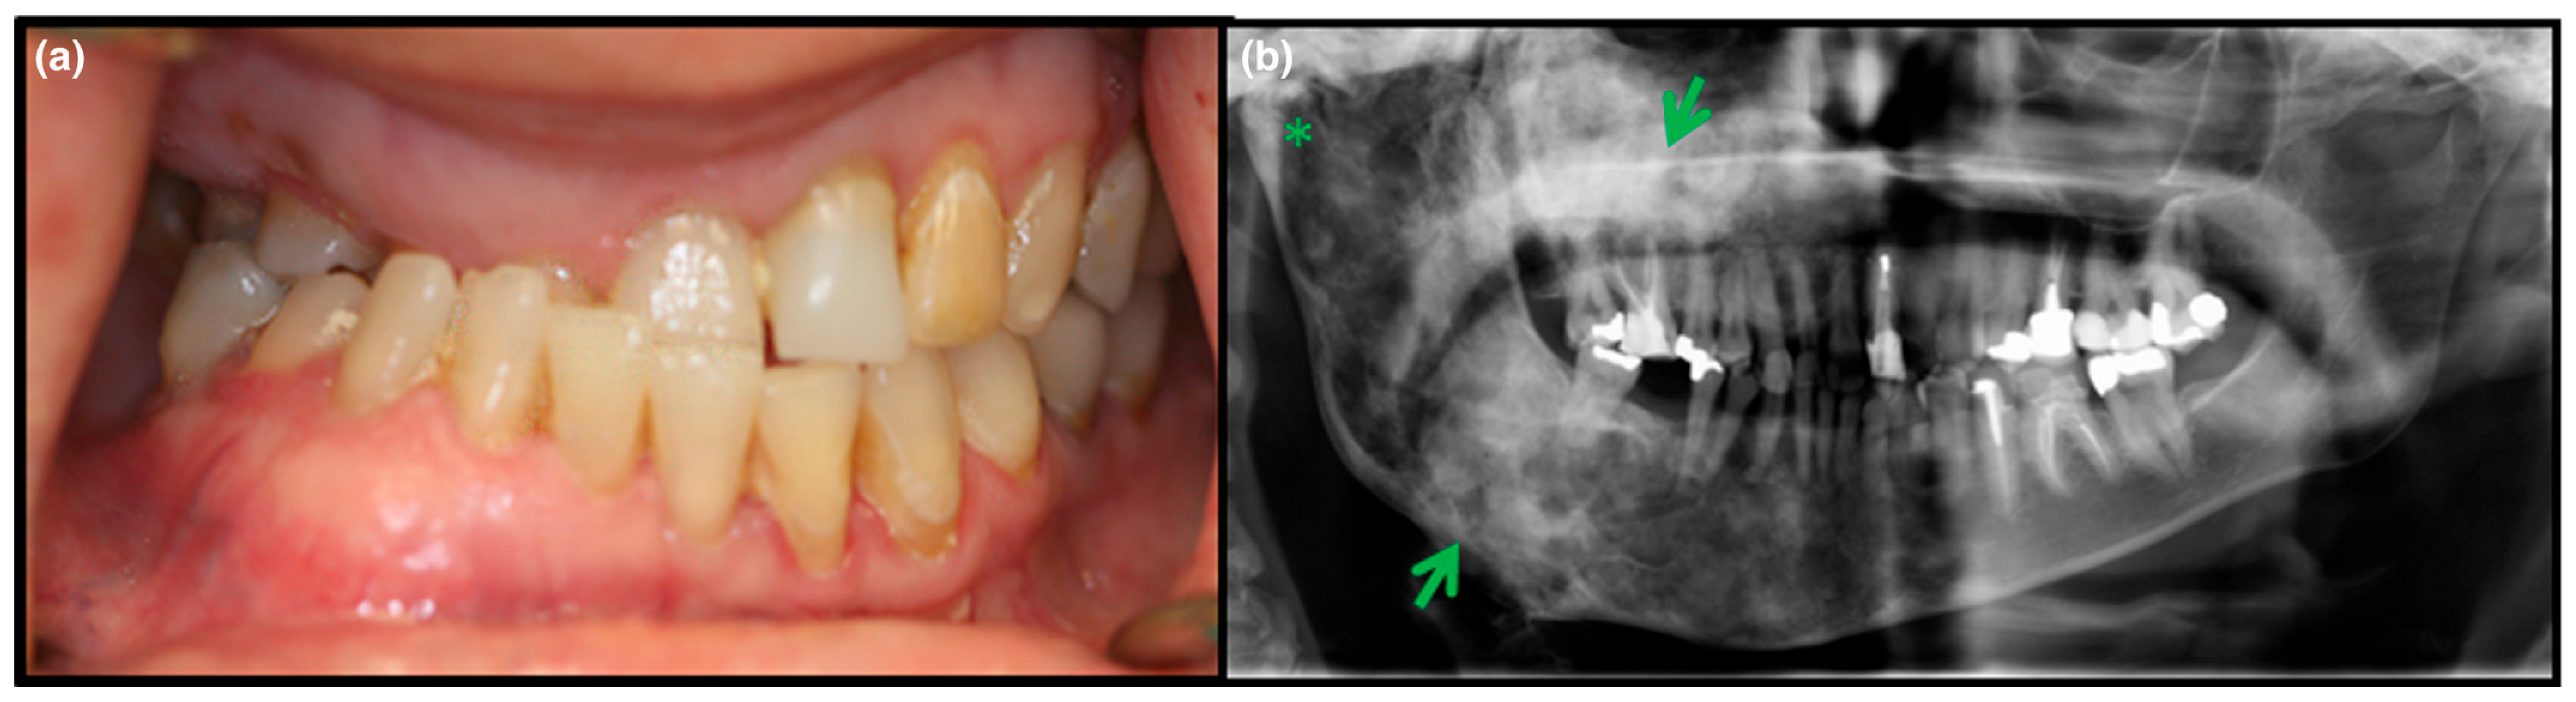

3.2. Axial/Craniofacial Manifestations of FD/MAS

- Akintoye, S.O.; Lee, J.S.; Feimster, T.; Booher, S.; Brahim, J.; Kingman, A.; Riminucci, M.; Robey, P.G.; Collins, M.T. Dental characteristics of fibrous dysplasia and McCune-Albright syndrome. Oral Surg. Oral Med. Oral Pathol. Oral Radiol. Endodontol. 2003, 96, 275–282. [Google Scholar] [CrossRef] [PubMed]

- Burke, A.B.; Collins, M.T.; Boyce, A.M. Fibrous dysplasia of bone: Craniofacial and dental implications. Oral Dis. 2017, 23, 697–708. [Google Scholar] [CrossRef] [PubMed]